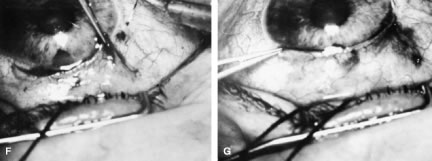

To obtain increasingly lower IOP, it is necessary to modify surgical technique (Table 15). By performing guarded filtration procedures so that the sutures can be released postoperatively, with the use of either laserable or releasable sutures, a lower final IOP can be obtained in some cases. This technique allows a bleb to develop that is similar to that seen in a full-thickness filtration procedure. Such blebs tend to be thin, polycystic, and located directly at the limbus, in contrast to those seen after classic trabeculectomy, which are thicker, lower, more diffuse, and more posterior. When antifibrosis agents (antimetabolites and corticosteroids) are added to procedures designed to develop full-thickness filtration, IOP tends to be sharply reduced.27–29 The blebs associated with the use of 5-fluorouracil (5-FU) and mitomycin are an exaggeration of the full-thickness type of bleb: Often, they are extensive, sometimes involving 360 degrees of the anterior surface of the globe, and the conjunctiva tends to be thin and completely ischemic.30–34